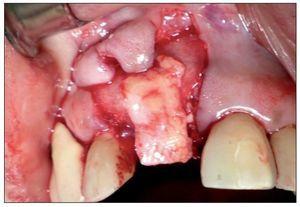

Figura 2. Ausencia total de tabla vestibular en relación con la pieza 8.

Se seleccionaron 8 pacientes dentro del Programa de Especialización en Periodoncia e Implantología de la Universidad Mayor. Cada uno de estos pacientes (2 hombres y 6 mujeres, rango de edad 21-56 años) presentaba indicación de extracción de una pieza anterosuperior, asociada a una pérdida de tejidos duros y blandos, la cual generaba una alteración estética importante en relación con las piezas vecinas, asociada a una pérdida total de la tabla ósea vestibular.

Figura 3. Sitio quirúrgico posexodoncia.